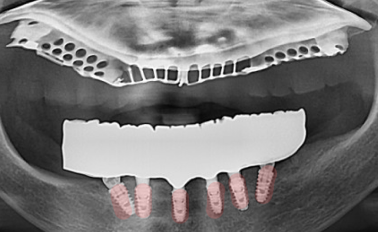

[원장 칼럼] 울산 전체 임플란트 비용이 고민된다면? ‘상악 틀니 + 하악 올온식스’가 답이 될 수 있습니다 이 글의 핵심 요약 대상: 울산에서 부모님 전체 임플란트 비용 부담으로 고민 ...

안녕하세요. 하루임플치과입니다. 부분틀니나 전체틀니를 오래 사용하시다 보면 “끼우면 아프고, 빼면 못 씹고…” 이런 양쪽 불편함 사이에서 &nbs...